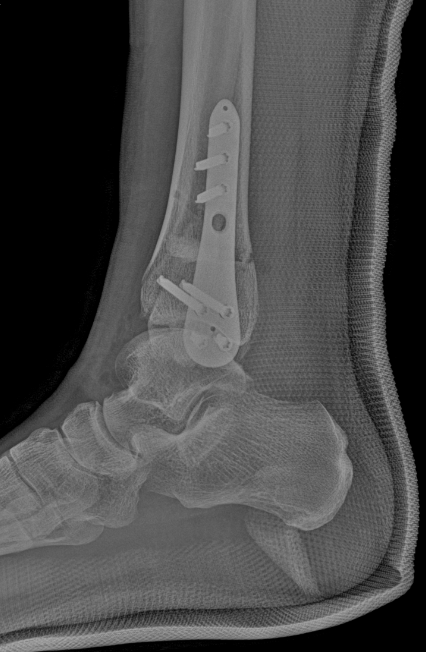

第三位是44岁的大姐,“脚脖子”痛加重了8个月,属于踝关节病中期。

术前踝关节侧位X线

术前踝关节正位X线

为了帮她留住自己的踝关节,团队做了踝上截骨术。

术后复查X线

术后复查侧位X线

这种手术通过调整踝关节的受力方向,改善关节负重情况,既能缓解疼痛,还能延缓病情发展,特别适合想保留自身关节的中青年患者。